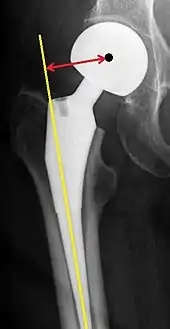

Femoral (neck) offset is defined as the perpendicular distance between the intramedullary or longitudinal axis of the femur and the center of rotation of the native or prosthetic femoral head. An offset of less than 33 mm is associated with hip dislocation.[82][83]